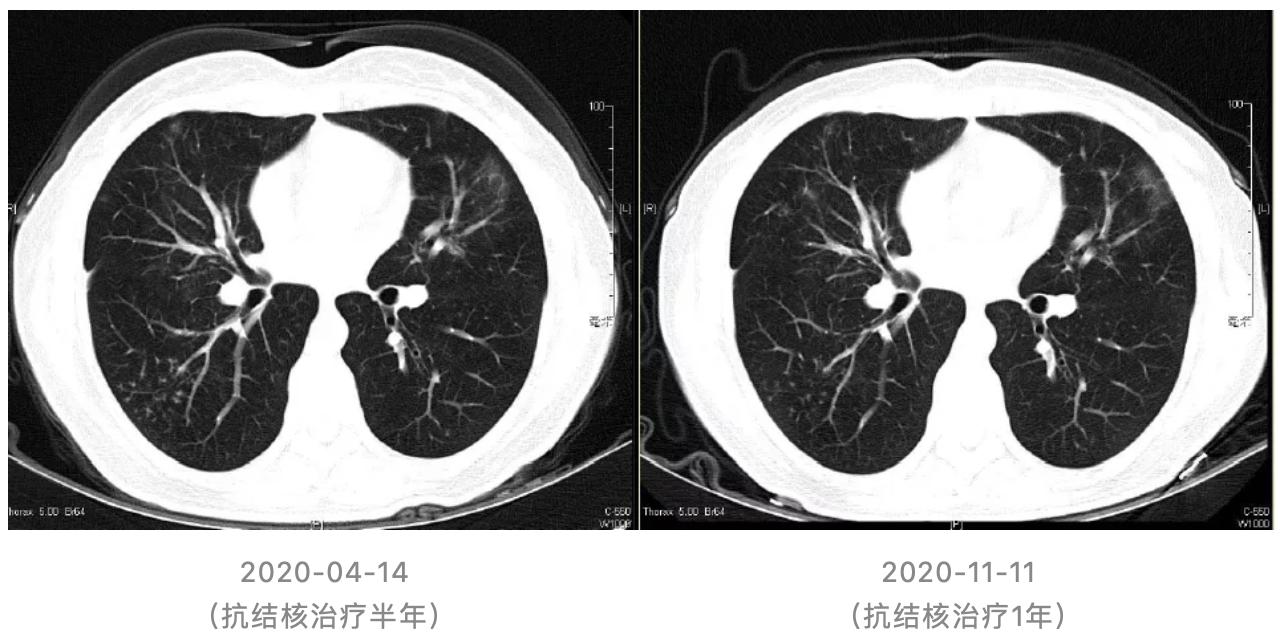

(1)抗结核治疗1月后随访胸部CT:

(2)抗结核治疗1年随访胸部CT:

我同意李教授的分析,这个病人诊断明确,是隐源性机化性肺炎,激素治疗约8月,目前右下肺出现新病灶,与之前病灶特征不同。另外,此机化性肺炎的影像学特点和通常看到的隐源性机化性肺炎不同,通常我们看到的隐源性机化性肺炎多为游走性的实变影,该患者闭塞性支气管炎的特征比较明显,支气管壁的增厚、扩张、扭曲,肺实质病变和炎症、小叶中央型小结节也存在,是闭塞性支气管炎伴机化性肺炎,这种表型比较少,可增加深呼吸相胸部CT协助诊断。此患者免疫抑制,免疫力低下,社区发病,有文献报告免疫力低下CAP和普通CAP病原体谱相同,但根据患者影像学特点和治疗反应,要注意特殊病原体感染。免疫抑制患者并发结核有两种情况:继发性肺结核,原来就存在潜伏肺结核,免疫力低下时复发;该病人我还是考虑原发性肺结核。

这次病例讨论选择的病例很好,极具挑战,临床医生对该病例的诊治付出很多,各位学员总结资料较全,分析思路清晰。就这个病例我来谈谈我的看法。对于这种病例还是要临床结合影像、病理的综合诊断。该隐源性机化性肺炎激素治疗有效,最初诊断明确。那么,对于机化性肺炎,肯定要鉴别是COP还是SOP,诊断前提要排除继发的一些因素,大家已经做了很多的鉴别。该病人第三段出现右下肺新发病灶,活检抗酸染色阳性,抗结核治疗有效。对于该病人第二段,病理提示炎症性改变,和第一段机化性肺炎病理改变还是有些不同,是用机化性肺炎解释,还是存在感染的因素,仍存在一些疑问,后续尚需要密切随访。